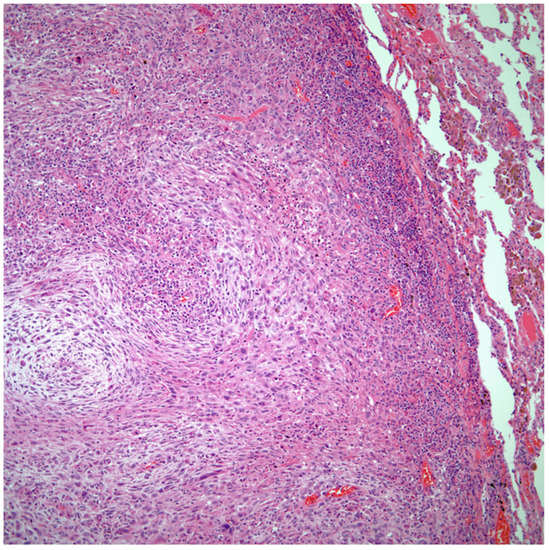

Sarcomatoid carcinomas: These tumors show a tightly packed spindle cell proliferation composed of slender cells with fusiform nuclei and inconspicuous nucleoli, replacing normal lung parenchyma. The tumors are well delimited but not encapsulated (Figure 1). Cellular atypia is variable and may show areas of mild to moderate to marked atypia. Mitotic figures also vary and may be inconspicuous or may be evident with the presence of atypical mitotic figures (Figure 2A,B). In high-grade tumors, the presence of necrosis and hemorrhage is prominent and is mixed with the neoplastic component. Important to recognize is that sarcomatoid carcinomas may be associated with areas of otherwise conventional non-small cell carcinoma such as adenocarcinoma or squamous cell carcinoma (Figure 3A,B). In addition, sarcomatoid carcinoma may also show the presence of bizarre giant cells admixed with the spindle cell component (pleomorphic carcinoma) (Figure 4).

Figure 1.

Sarcomatoid carcinoma of the lung showing a well circumscribed tumor replacing lung parenchyma.